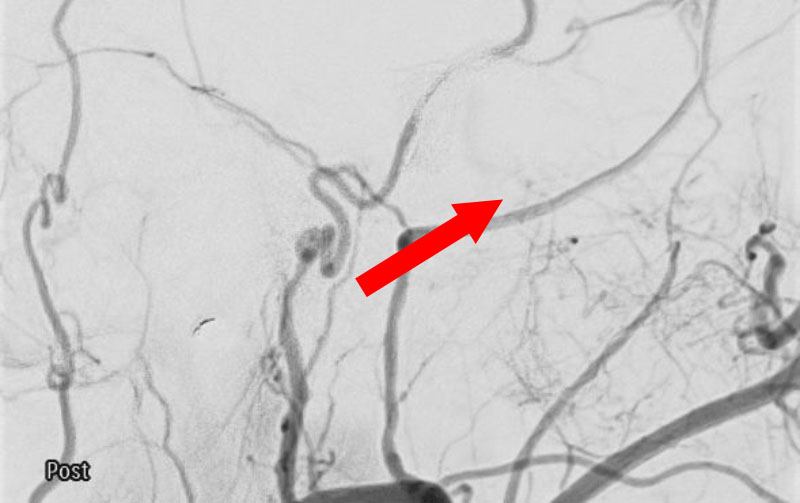

No.1591 手術後

硬膜動静脈瘻

50代

救急外来